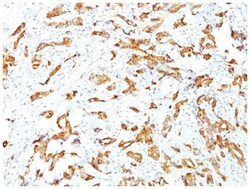

HSP27 Monoclonal specifically detects HSP27 in Human, Mouse, Rat, Chicken, Chimpanzee, Monkey, Sheep samples. It is validated for Western Blot, Flow Cytometry, Immunohistochemistry, Immunocytochemistry/Immunofluorescence, Immunohistochemistry-Paraffin.Specifications

| This MAb reacts specifically with heat shock protein HSP27 in human and monkey tissues and cell lines such as MCF-7. HSP27, also referred to as the Estrogen-Regulated 24K protein and HSP28, is one of several small heat shock proteins produced by all organisms studied. HSP27 synthesis is induced by elevated temperature, as well as by estrogen in hormone responsive cells. Interestingly, human HSP27 also shares greater than 50% homology with low molecular weight Drosophila HSPs and mammalian alpha-crystalline lens protein. Because of the estrogen responsive nature of HSP27, this protein has been studied extensively in human estrogen responsive tissues such as cervix, endometrium and breast tissue. Therefore HSP27 may be useful in classifying various hormone sensitive tumors. |